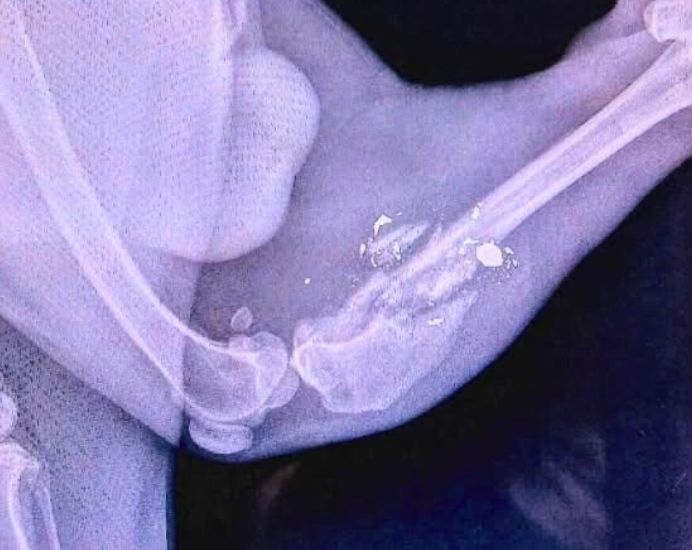

He was limping and not putting any weight on one of his legs, so our medical team had Kylo X-rayed for an assessment. The X-rays revealed that Kylo’s rear left tibia and fibula have been completely shattered near the knee, with bullet fragments throughout the fracture. We have no idea when, how or why this happened, but we do know the damage is so severe that he cannot use the leg at all. The best chance for Kylo to live a happy, pain-free life is amputation surgery, so he can run around without a bum leg that no longer works for him.